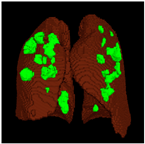

- By using a 3D segmentation architecture on a CT-scan, in addition to being able to help the COVID-19 disease diagnosis process, the 3D output generated from the model can help medical personnel determine the severity of the disease, such as mild, moderate, or severe, through a 3D infection projection that can be easily seen from the output model that generates a file in 3D shape.

Based on the results of the evaluation metrics for each architecture in Table 5, surprisingly, 3D UNet is better than the other six methods. Compared with the 3D VGGUNet architecture with transfer learning, which achieved the second best result on average, 3D UNet improved by 0.37%, 0.23%, 0.03%, and 0,19% in IoU score, Dice score, accuracy, and F1-score, respectively. Although 3D UNet has the best evaluation of metrics compared to other architectures, 3D UNet has the longest maximum learning iteration process of 1663, in contrast to other architectures, which are modifications of 3D UNet, and which have an average maximum learning iteration of 278. Of the seven models that have been tried, 3D DenseUNet obtained first place as the architecture with the fastest learning time, ±4459 s and ±6539 s without transfer learning and using transfer learning, respectively. The 3D UNet architecture stays in the second last position with a learning process time of ±17,217 s, and for the position of the architecture that has the longest training process, it is the 3D VGGUNet, with transfer learning reaching ±23,200 s. The comparison of loss training and testing on the 3D UNet learning process for the lung segmentation is shown in Figure 4. Furthermore, in Table 6, the comparison of ground truth and the prediction results of the 3D UNet model in 2D (slice) and 3D projections for this binary-class segmentation case can be seen.

Table 6.

Comparison between ground truth and prediction results of lung segmentation with 3D UNet architecture.

Table 8.

Comparison between ground truth and prediction results of lung and infection segmentation with 3D UNet architecture.